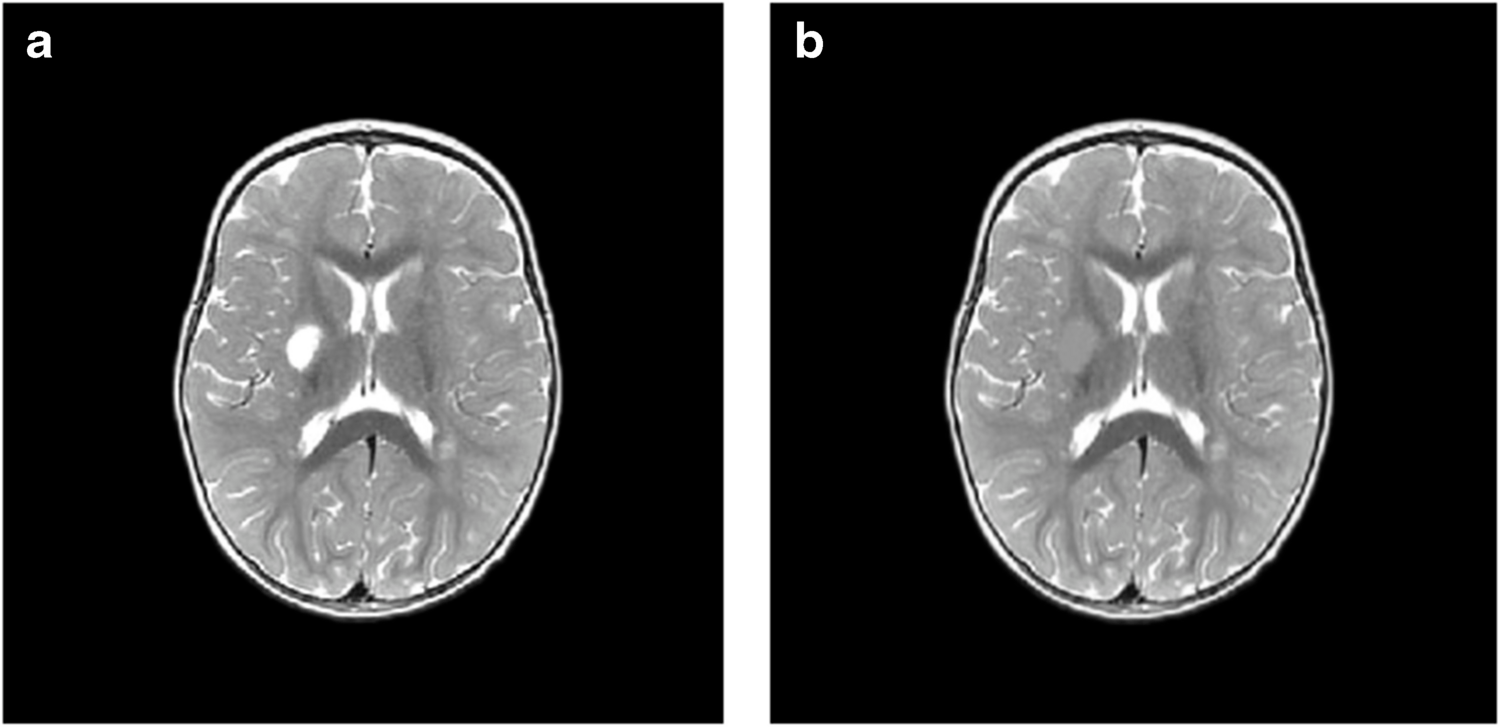

Ишемическое поражение в зоне кровоснабжения правой средней мозговой артерии (а) и его ручная разметка (b) на срезе.

© Korotkova, E.V., Kulikova, S.P., Kotyusov, A.I. et al. Voxel-based morphometry of brain MRI: first results in pediatric ischemic stroke cohort. Neurosci Behav Physi 55, 327–339 (2025).